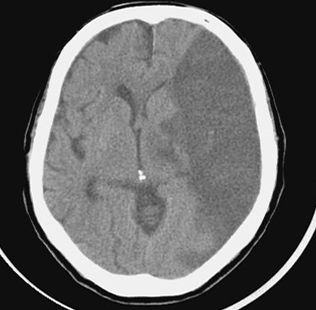

수술로 대뇌동맥이 심하게 좁아지면 스텐트나 경동맥내막절제술을 통해 동맥경화 자체를 없앨 수 있다.

혈전 용해제는 약물 치료에 사용됩니다. 뇌의 막힌 혈관에 혈전용해제를 도포하여 혈전을 녹이는 치료법입니다. 동맥 내 및 정맥 내 투여의 두 가지 방법이 있습니다. 동맥내 투여 방식의 장점은 즉시 효과를 볼 수 있다는 것이지만 단점은 시간과 노동력이 많이 든다는 점이다. 뇌졸중 후 3시간 이내에 사용할 수 있는 정맥주사법은 간편하다는 장점이 있지만 즉시 확인이 어렵다는 단점이 있다.